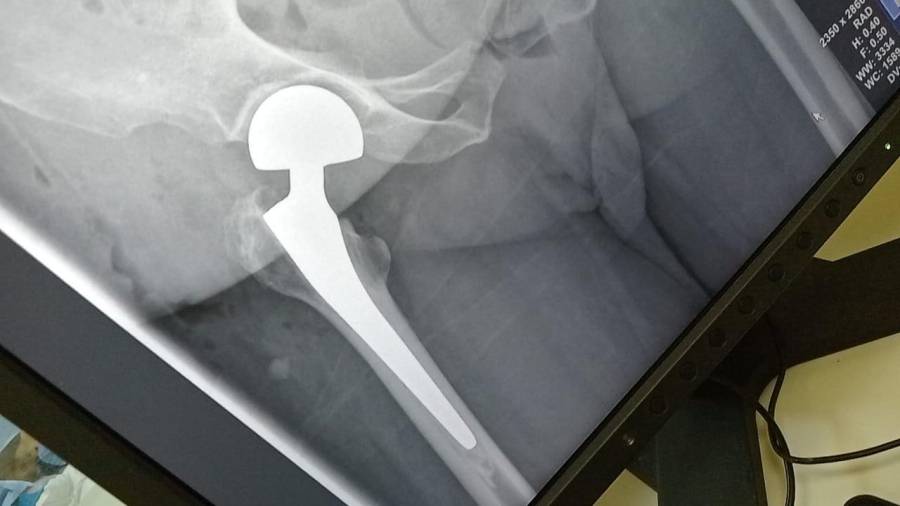

- إجراء عمليات جراحية معقدة و دقيقة في مجال العظام و المفاصل و الكسور و الإصابات ، رغم الضغط الكبير على المستشفى و أعداد المراجعين الكبيرة.

- تطبيق تقنيات جراحية حديثة و متقدمة، و ذلك في ظل التحديات التي يواجهها الفريق بسبب أعداد المرضى و المراجعين الكبيرة.